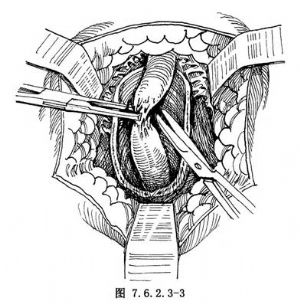

2.遊離尿道狹窄段 縱行切開球海綿體肌,顯露包繞於其內的球部尿道。沿尿道海綿體表面向兩側及上下將尿道從球海綿體肌中游離出來。然後用一組織鉗在尿道瘢痕處鉗夾提起,在尿道海綿體與陰莖海綿體之間,用剪刀分離,使尿道瘢痕狹窄段及其近遠側部分正常尿道與陰莖海綿體完全分開(圖7.6.2.3-3)。